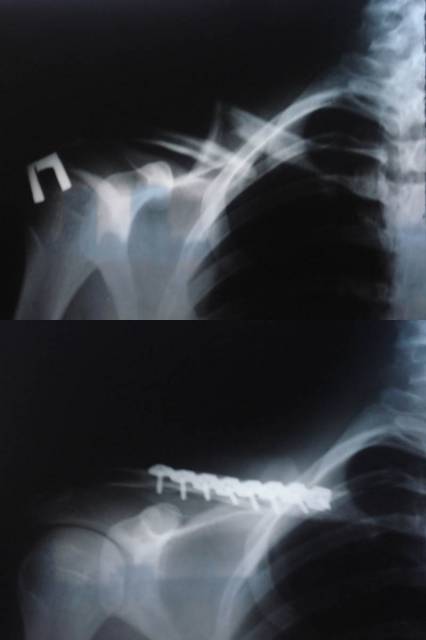

Главная > Железки > Поломки и падения

падение и поломка

пока открыть новый раздел "МОЯ ПОЛОМАНАЯ КЛЮЧИЦА" Из поломок половина фоток пойдет туда))